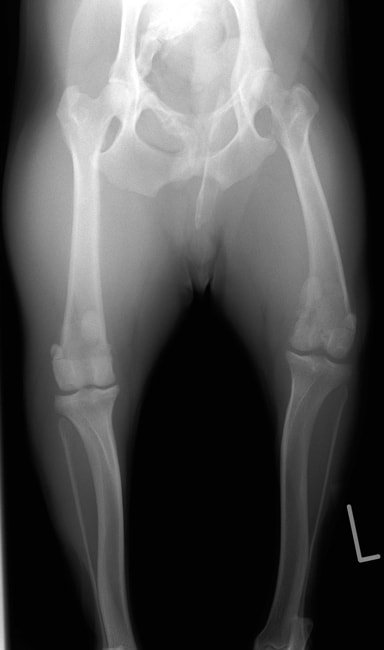

■ 症例22 ポメラニアン 1歳5か月 去勢雄

左後肢の挙上を主訴に来院した。整形学的検査、レントゲン検査より左右の膝蓋骨脱臼(左GradeⅡ〜Ⅲ、右Grade Ⅱ)を認めた。また、脛骨の前方引き出し試験の際に、引き出し兆候は認められないものの、疼痛が認められたため、前十字靭帯の損傷が疑われた。術中における、目視および関節内の操作によって、前十字靭帯の損傷や過伸展といった異常が認められなかったため、膝蓋骨脱臼の整復のみ実施した。手術手技は縫工筋及び内側広筋の解放、脛骨粗面の外側転位、滑車ブロック形造溝術、内外側関節包の縫縮を実施した。本症例は跛行もなく経過良好である。しかし、頸骨高平部の角度(TPA)が 右26.2°、左24.9°であり、解剖学的に前十字靭帯損傷のリスクが高いことから今後の経過に注意が必要である。